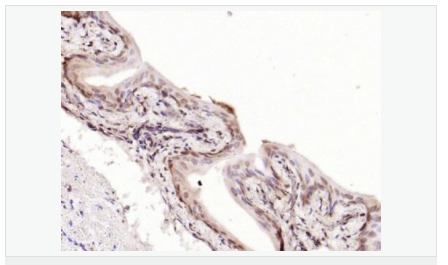

| 產品應用 | WB=1:500-2000 ELISA=1:5000-10000 IHC-P=1:100-500 IHC-F=1:100-500 Flow-Cyt=1μg /test IF=1:100-500 (石蠟切片需做抗原修復) not yet tested in other applications. optimal dilutions/concentrations should be determined by the end user. |